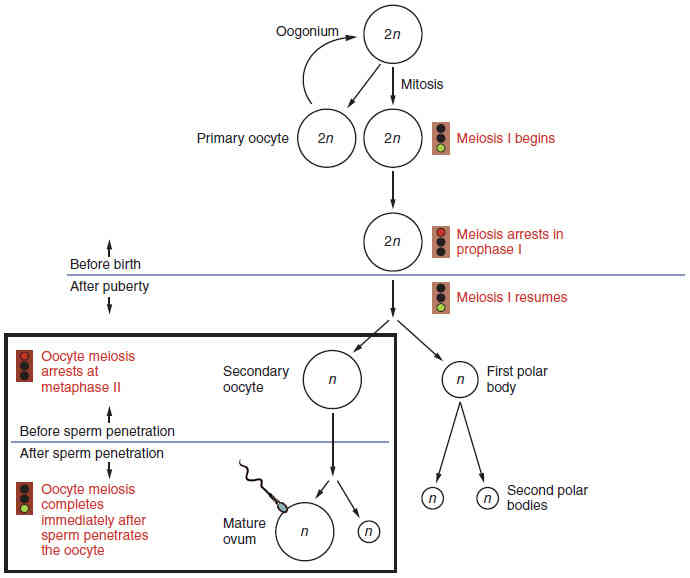

This page is under construction. For now, it is just a resource of the images found in the OpenStax Anatomy and Physiology Handbook. It wil slowly change into a revision tool. Each slide has a number. Use this to refer to the slide. When completed, it will have an unlabelled section, with labelled slides in parallel. On the unlabelled slides, write your answer and use the labelled slide to assess yourself. Keep track by also noting the number on each slide. Improvement at each attempt is important, more so than full marks on a first attempt.